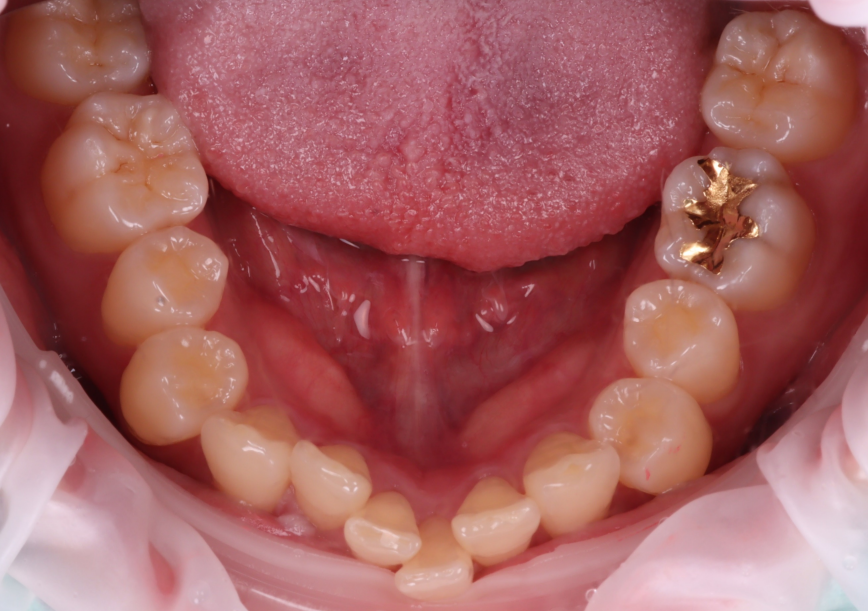

또, 2개 치아 모두 입천장 쪽으로 기운 형태였어요.

그 점도 감안해 바깥쪽으로 풍융하게 보이게 만들어 전체적으로 가지런하게 보일 수 있도록 계획했습니다.

촬영일 : 251120